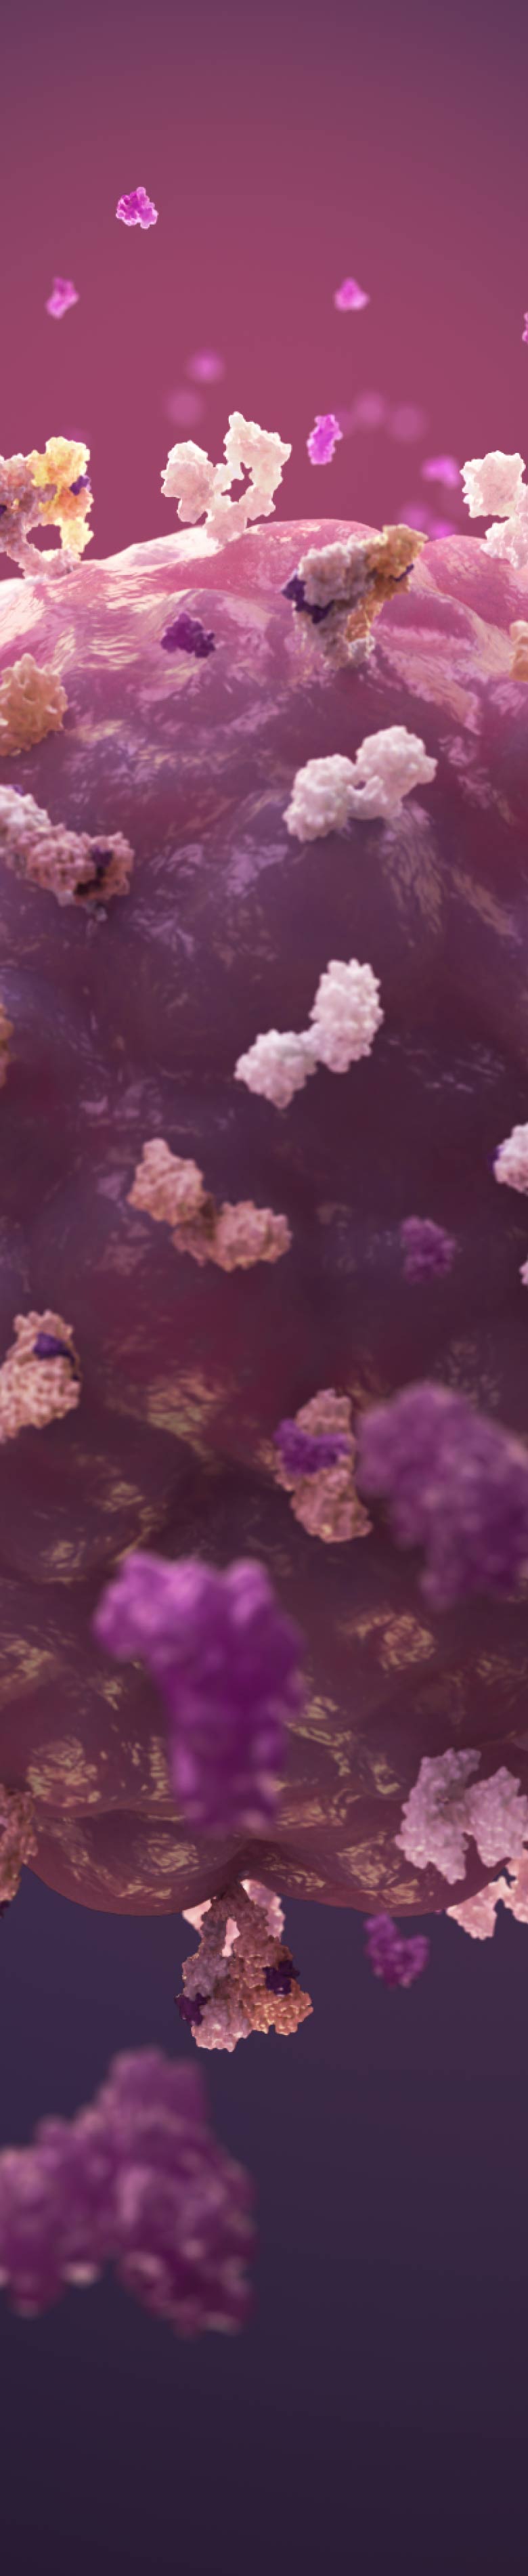

HER3/ERBB3 is one of the four members of the HER family of receptor tyrosine kinases1,2

- All four members of the HER family share a common molecular structure and play a role in normal cell biology1–4

- Members of the HER family are expressed widely in numerous cell types, including epithelial, neuronal, and mesenchymal cells1

- HER3 activation depends on heterodimerization with another receptor to induce downstream signaling pathways4

- Although HER2 is generally its preferred dimerization partner, HER3 can dimerize with other receptors in the HER family2,4

- HER3 also dimerizes with some non-HER family receptors, including MET and FGFR24,5

HER3 dimerization and activation are involved in normal cell physiology1

- In normal physiology, binding of the ligand (heregulin, a neuregulin family member) leads to dimerization1

- After dimerization, HER3 relies on its dimer partner’s tyrosine kinase activity, which can then phosphorylate one or more of the tyrosine residues on its intracellular kinase domain4, 5

- This leads to activation of pathways that regulate normal cell division, proliferation, and differentiation4,5

HER3 expression is higher on tumor cells compared with normal healthy cells22

HER3 in Cancer Cells

- HER3 activation can sustain several oncogenic signaling pathways, including PI3K/Akt, MAPK, JAK/STAT, and SRC1,2,23,25

- Amplification/mutation/overexpression of HER3 ligands and dimerization partners, including HER and non-HER RTKs, such as MET, can promote bypass signaling through activation of these signaling pathways2,25−29

- Increased HER3 signaling or expression may play a role in the initiation of signaling activity leading to increased cellular proliferation, invasion, and migration in multiple tumor types, including breast, HNSCC, colorectal, and lung cancers1,2,4,31,32